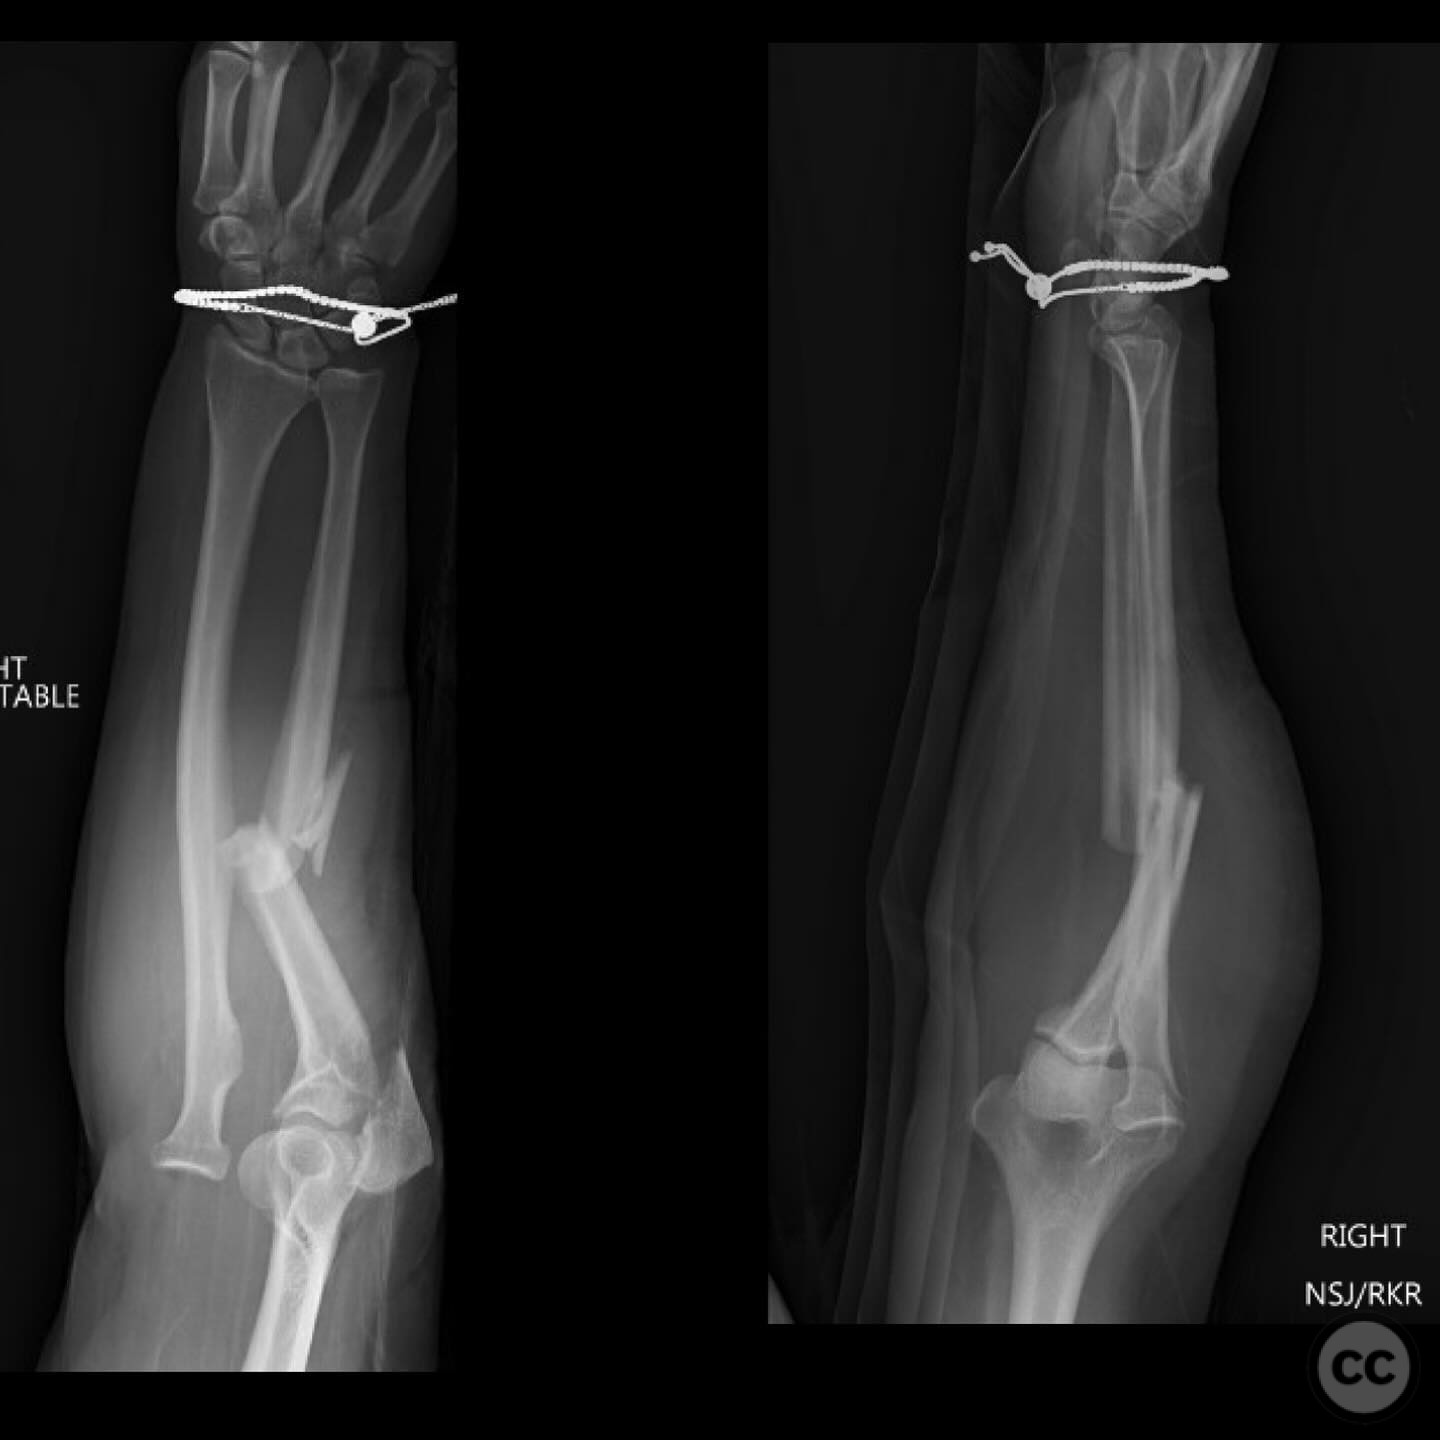

Sep 27 2024

By Dr Ed Oates

Monteggia Fracture with Segmental Ulna S...

Schleswig Holstein, Germany

Ulna - AO/OTA 2Ux